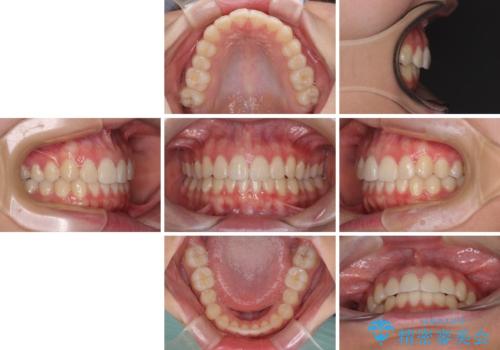

- 口元のデコボコを気にして来院された患者様です。

前歯の捻れにより口元が閉じにくくなっていたため、歯列全体の側方への拡大と、歯と歯の間を少し削ってスペースを獲得することとしました。

ゴムかけをしっかりと行ってもらい、スッキリとした口元に仕上げることができました。